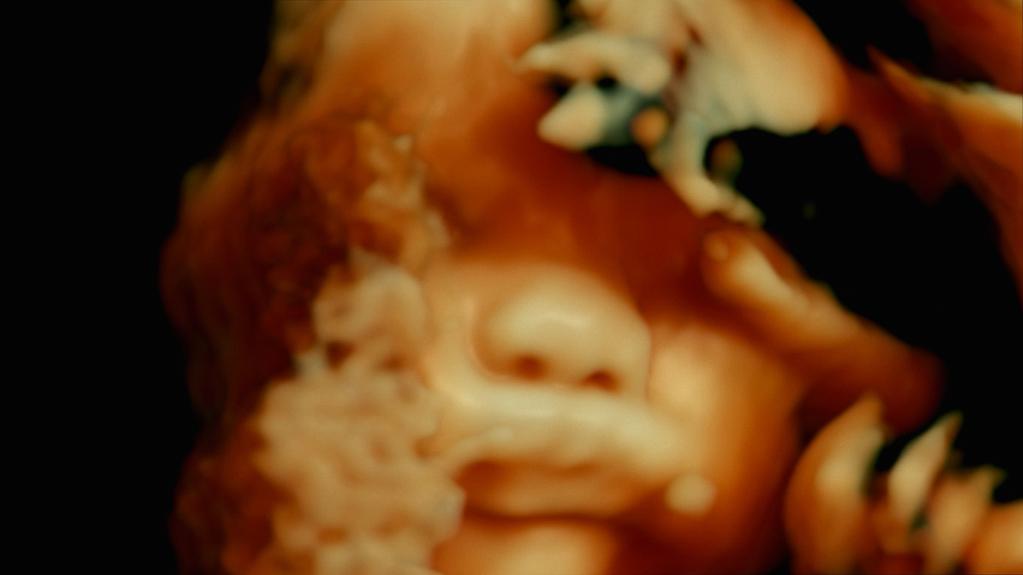

The Son